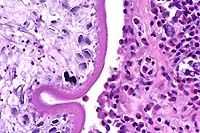

- The lung has multiple, discrete, subpleural granulomas which

each contain a single immature cestode that lacks a bladder wall.

The cestode larvae are nonsegmented and contain an invaginated

scolex. Occasional sections of the larvae show the presence of

suckers in the invaginated canal. Larvae have multiple small

lightly basophilic calcareous corpuscles. The reaction is characterized

by fibrous septal thickening, type II pneumocyte hyperplasia

and a mix of inflammatory cells consisting of eosinophils, macrophages,

plasma cells, and lymphocytes. A layer of degenerate inflammatory

cells lies adjacent to the cestodes. The pleura is thickened

by chronic pleuritis.

- Case 8-1 . Lung. The 2x view shows 3 profiles of cestode

larva surrounded by a dense inflammatory infiltrate forming a

granuloma adjacent to the pleura surface. Surrounding alveoli

have mild alveolar emphysema and thickened alveolar septa. At

40x, multiple calcarious corpuscles (blue bodies with clear halos)

are scattered within the mesenchyme of the larva. The tegument

has a thick eosinophilic, 15-20u, smooth surfaced cuticle. The

surrounding interstitium is fibrotic with moderate numbers of

infiltrating eosinophils and fewer macrophages and lymphocytes.